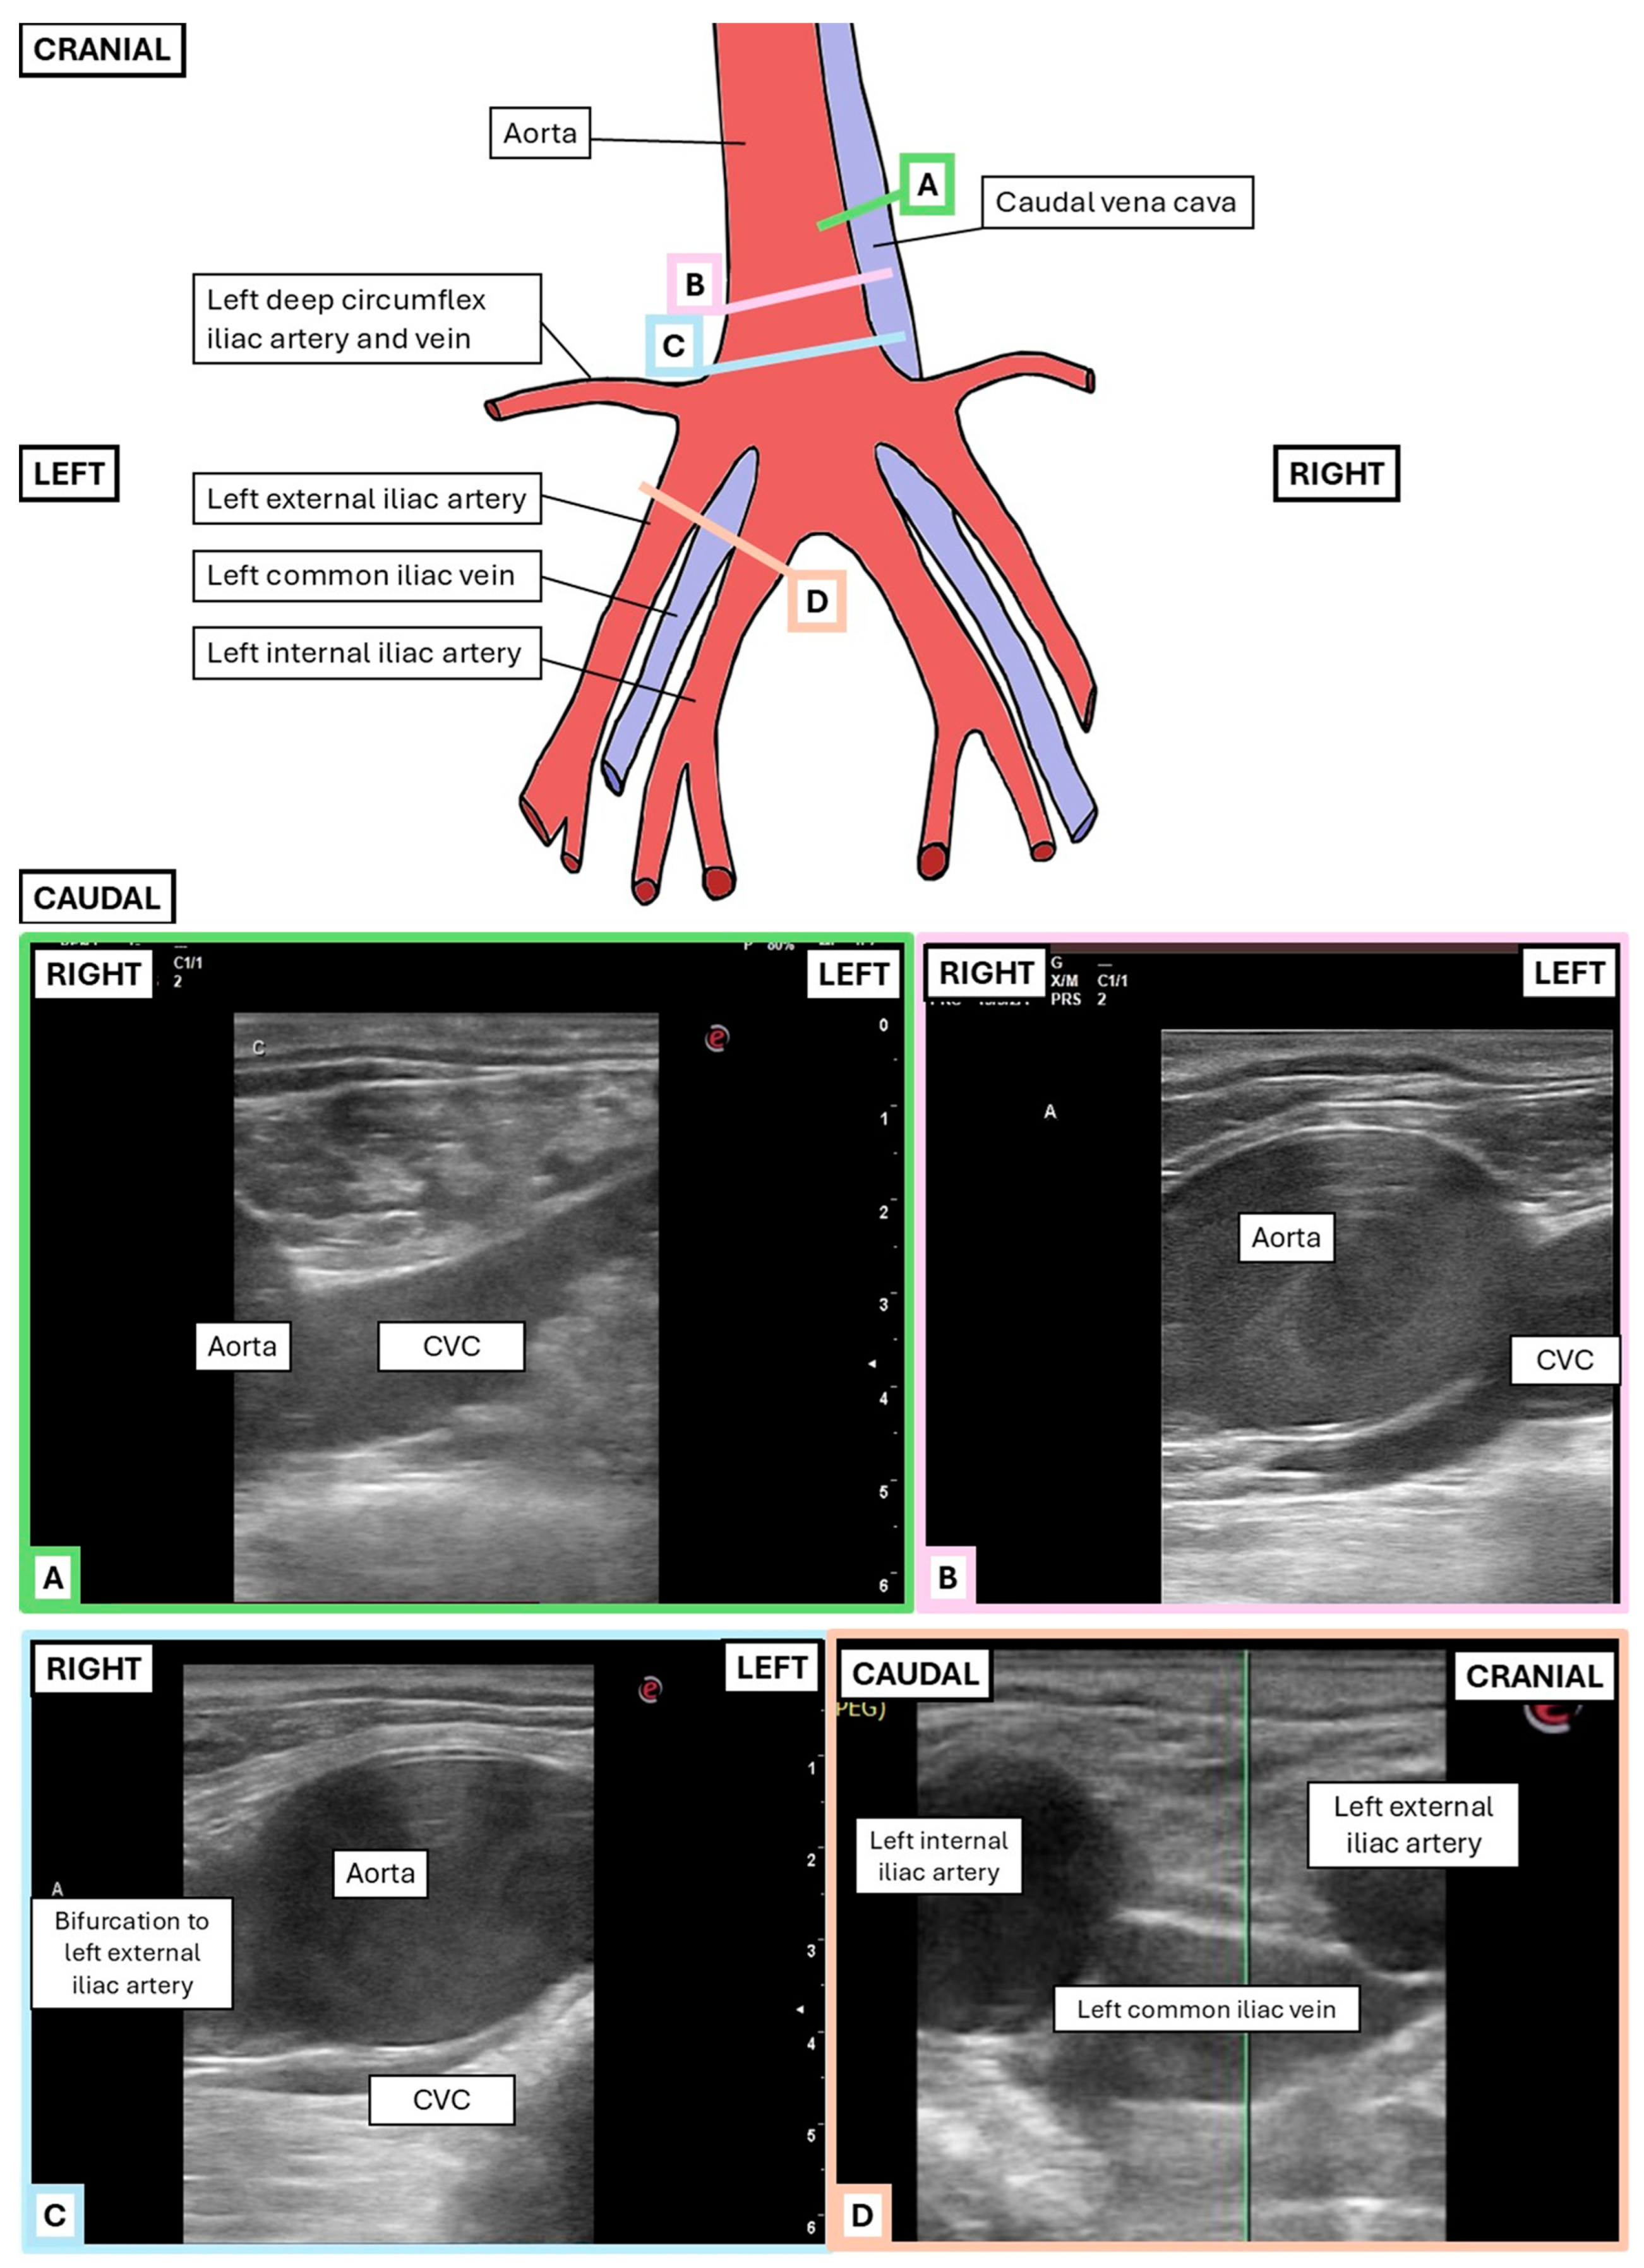

2.2.1. Transrectal Ultrasonographic Technique

2.3.2. Transrectal Variables

3.2. Transrectal Variables